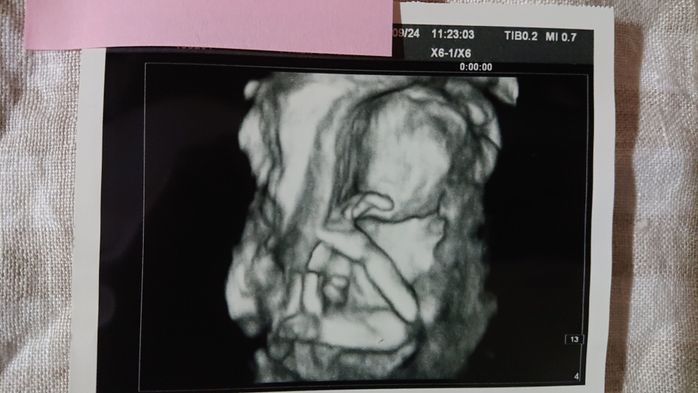

《妊娠18週目のエコー写真》

こちらは妊婦健診の日とは別に、別料金で撮影したエコー写真です。立体的でより精密に赤ちゃんをとらえることができます。専門の医師に臓器等も含め、状況をじっくり見てもらったところ、「異常なし」とのことでホッと一安心。妊婦健診の時に、「たぶん女の子かな」とは言われていましたが、ここで性別も「女の子」とほぼ確定状態になりました。